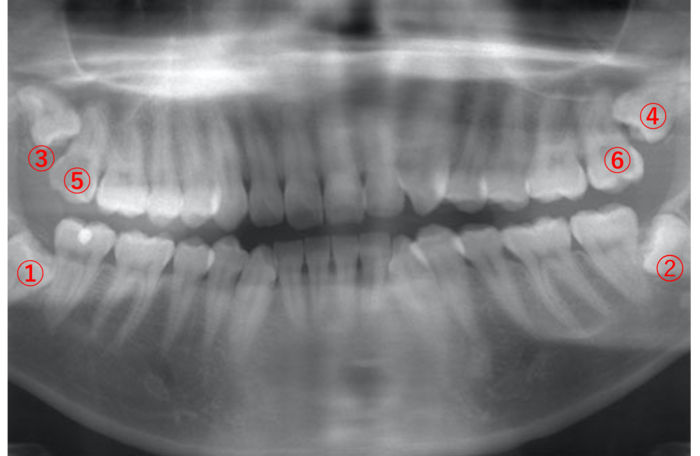

(27歳男性)

| 年齢・性別 | 27歳・男性 |

|---|---|

| 主訴 | 親知らずに食べ物が挟まる。 |

| 歯ブラシ | 毎日歯を磨いている。汚れが残っていて、うまく磨けていない。 |

親知らずの周りには、汚れがびっしりと付着しています。

画像➁の親知らずは横向きに生えているため、食べる度に手前⑤の歯との隙間に食べ物が挟まり、虫歯になっています。

このような場合は、早めに親知らずを抜いて手前⑤の歯の虫歯を治療した方が良く、また②の親知らずを抜くと上の④の親知らずが下がってくるため、一緒に抜いた方が良いです。

そして反対側①の親知らずは、顔を出しているので、歯ブラシが上手くできないのであれば抜いた方が良いこと、③に関しては、顔を出してない親知らずのため、無理して抜かなくても良いと説明しました。

食べ物が挟まる形態の親知らずは、隣の歯に影響を及ぼすため、抜いた方が良いことが多いです。